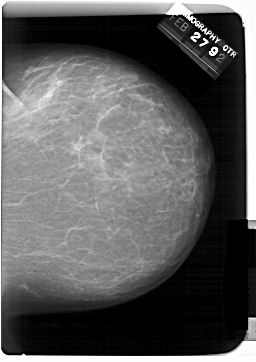

A_1389_1.LEFT_MLO

LEFT_MLO LINES 6361 PIXELS_PER_LINE 5191 BITS_PER_PIXEL 12 RESOLUTION 43.5 OVERLAY